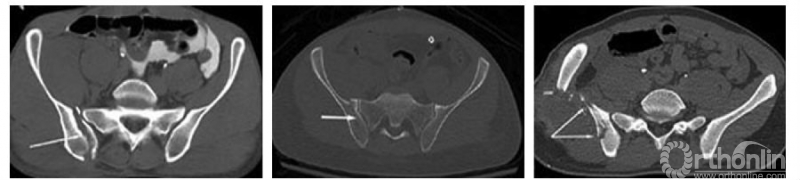

新月形骨折病理解剖学分型系统的建立

骶骨在骶髂关节水平主要有3道明显隆起的骨嵴,即骶骨耳状面前缘(骶骨翼)、骶骨耳状关节面后缘(骶骨侧嵴)和后方骶骨外侧嵴。我们通过总结65例新月形骨折患者的骨折特点发现,新月形骨折的髂骨骨折线进入骶髂关节的位置与骶骨上隆起的骨嵴及髂骨上相应的凹陷密切相关。

图4 骶骨侧方的3道骨嵴(红色虚线):①骶骨耳状面前缘(骶骨翼);②骶骨耳状关节面后缘(骶骨侧嵴);③后方骶骨外侧嵴。其中第①、②道骨嵴在侧方挤压应力作用下,可能起“支点”作用,第③道骨嵴大量韧带附着,其附近的骨折主要表现为髂骨内板的撕脱骨折。

新月形骨折病理解剖学分型以骶骨的骨性标志为分界,将新月形骨折分为三型:

Ⅰ型,新月形骨折线在骶骨翼水平进入骶髂关节;

Ⅱ型,新月形骨折线在骶骨侧嵴水平(真性骶髂关节面后界)进入骶髂关节;

Ⅲ型,新月形骨折线在骶骨侧嵴后方水平进入骶髂关节。

新月形骨折病例解剖学分型Ⅰ型:

图5 A~C.横断面特点:内板骨折线(红色箭头所指)在骶骨翼尖端(红色三角形所指)层面附近进入骶髂关节,分型不会随着横断面的不同层面变异,各层面髂骨骨折线均位于骶骨翼尖端水平,横断面不同层面髂骨骨折线均位于骶骨翼尖端附近;D.冠状位特点:新月形骨折骶髂关节脱位(红箭头所指)发生在冠状位前几个层面的骶髂关节的下半部分